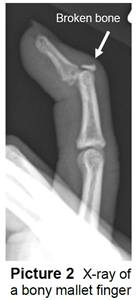

- It can sometimes break off a piece of bone. This is called a bony mallet (Picture 2). If the bone doesn’t break but the tendon tears, it’s called a soft tissue mallet.

Your child’s doctor or health care provider will ask what happened, examine the finger, and take an X-ray to see if the bone is broken.